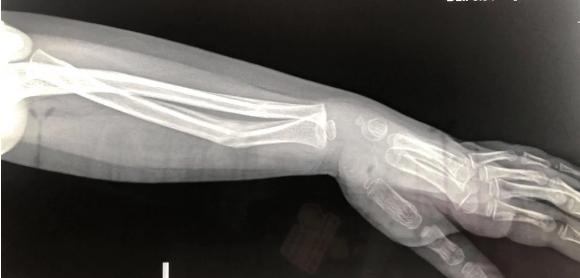

În radiografia pe care doctorul o văzuse, oasele antebrațului subțire al fetiței, învelit în umbra ghipsului, apar strâmbe. Un fapt pe care părinții îl vor afla abia 3 săptămâni mai târziu.

Așa că soluția a rămas revenirea periodică la control. Ultima radiografie, efectuată în urmă cu o săptămână, surprinde aceeași angulație în antebrațul fetiței cu care a plecat din Spitalul de Copii din Cluj-Napoca.